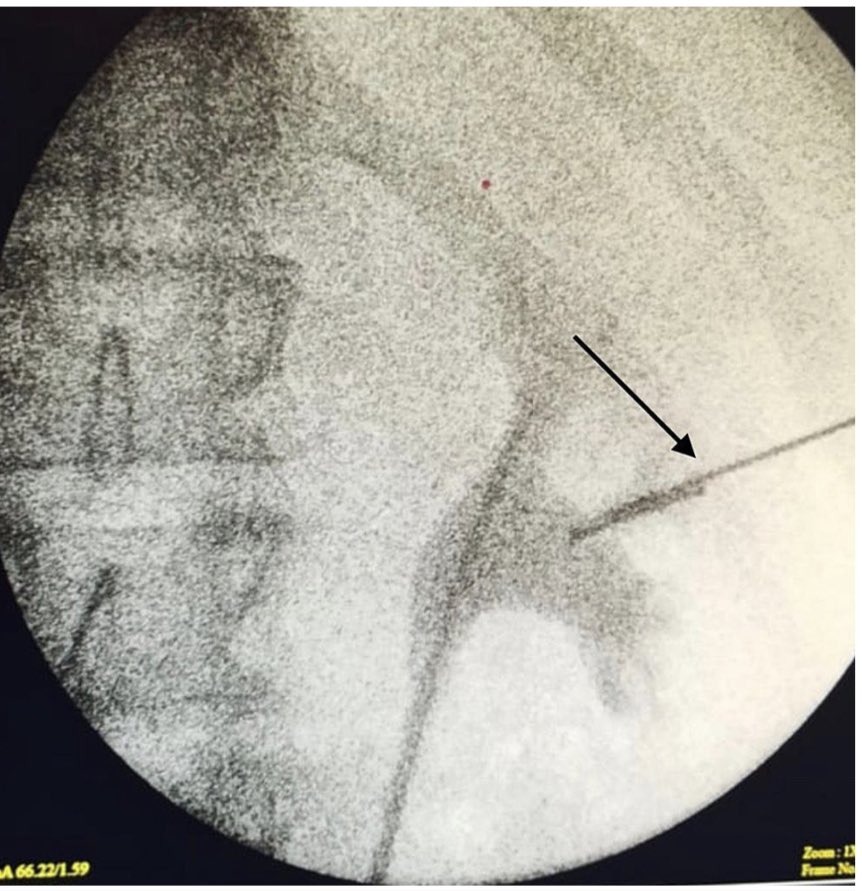

💡After Thousands of Lithotomies … here it is ( Neuropraxia ) …

〰️ It could happen …

🔴 Nail Gun Penetrating #Renal Injury ..

🔴 How do you react as #Endourologist to extract metallic #nail from #renal collecting system by PCN 🙂…

🔴 Simply Amazing